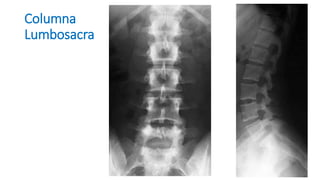

Proyecciones de Columna

Columna Torácica

Columna

Lumbosacra